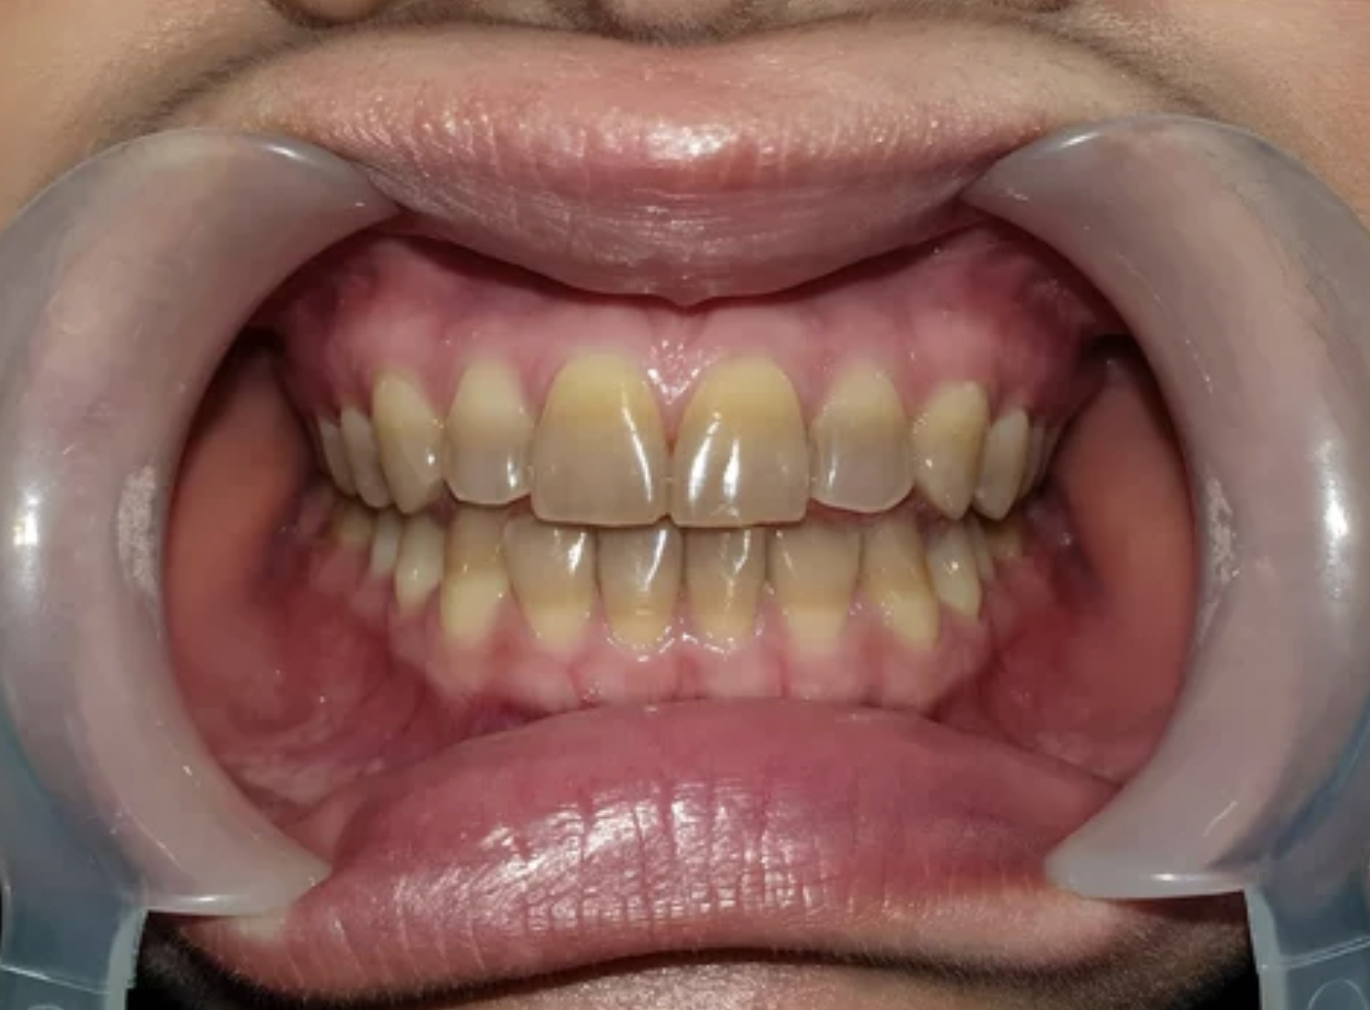

歯が黄色いのは不健康のサイン?

歯が黄色いとなぜだか不健康だと感じることはありませんか?

歯の黄ばみや着色の要因には、食べ物や飲み物、タバコなどの外部要因と歯の内部の組織からくる内部要因があります。

歯の黄ばみや着色を改善するためには、要因が外部要因なのか、内部要因なのかを見極めて適切な方法を選択することが大切です。

黄色い歯が与える印象

黄色い歯は、歯科において歯が汚れている状態を示すことが多いです。

歯垢や歯石が長時間放置されると、歯が黄色くなり、虫歯や歯周病につながります。